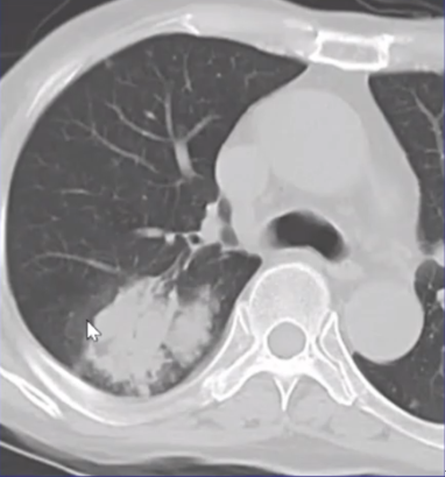

患者经过抗曲霉菌治疗后,肺部病变逐步缩小为薄壁空洞,病灶基本吸收(图7)

图片

图7  治疗后胸部CT(2014-10-08)